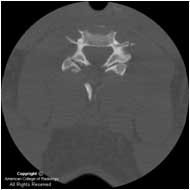

- Moderate need – a CT scan for adult appendicitis